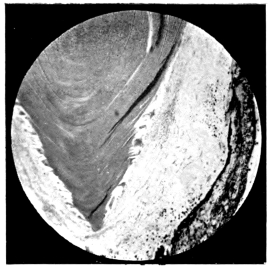

PLATE III.

16.

ABUNDANT EXUDATE INTO VITREOUS CAVITY

curly bracket span

42

17.

LENS FIRMLY FIXED BY ORGANIZED EXUDATE

18.

LENS FIRMLY FIXED BY ORGANIZED EXUDATE, BUT IN UNUSUAL POSITION

19.

TOTAL DETACHMENT OF RETINA, WITH CYST FORMATION

20.

RECLINED LENS LYING IN FRONT OF THE HYALOID BODY

21.

RECLINED LENS LYING IN FRONT OF THE HYALOID BODYxii